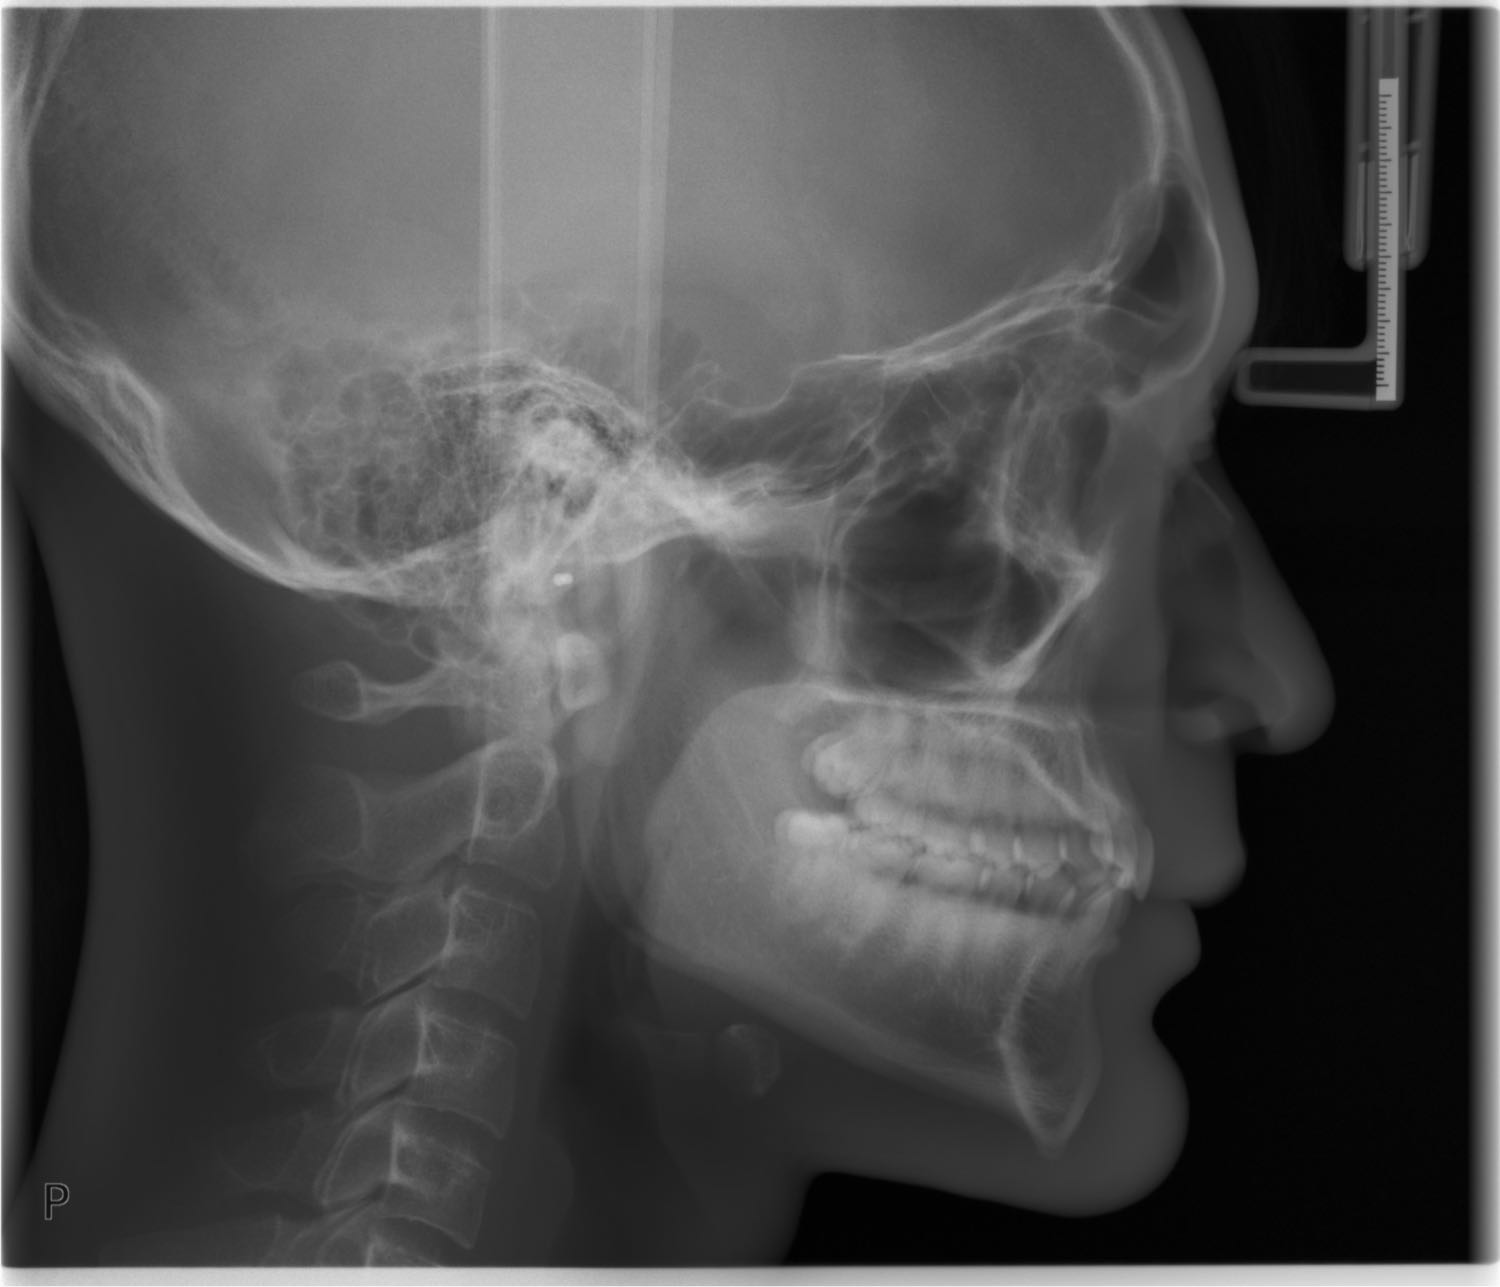

ปัญหาของผมคือ "คางยื่น" ครับ กังวลมาตั้งแต่เด็ก ช่วงนี้หารายได้ได้แล้วเลยอยากมาศัลยกรรมครับ คิดมาตลอดว่าเป็นที่กระดูกส่วนคาง แต่พอไปปรึกษาหมอ(หมอทันตกรรม) และ X-ray ดูแล้ว กระดูกไม่ได้ยื่นเท่าไหร่ แต่สิ่งที่ทำให้คางยื่น คือชั้นเนื้อเยื่อ/กล้ามเนื้อปลายคางมันหนา